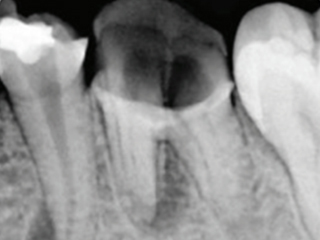

신경치료 중 치료는 마지막까지 하지 않고 방치하게 되면 치아는 신경이 없는 상태로 방치되는 것이기 때문에 까맣게 변색이 됩니다.

뿌리가 곪으면서 턱뼈 내부에 농 주머니가 생기게 됩니다.

치아가 녹아버리거나 부러져버리는 상황에 이르게 됩니다.